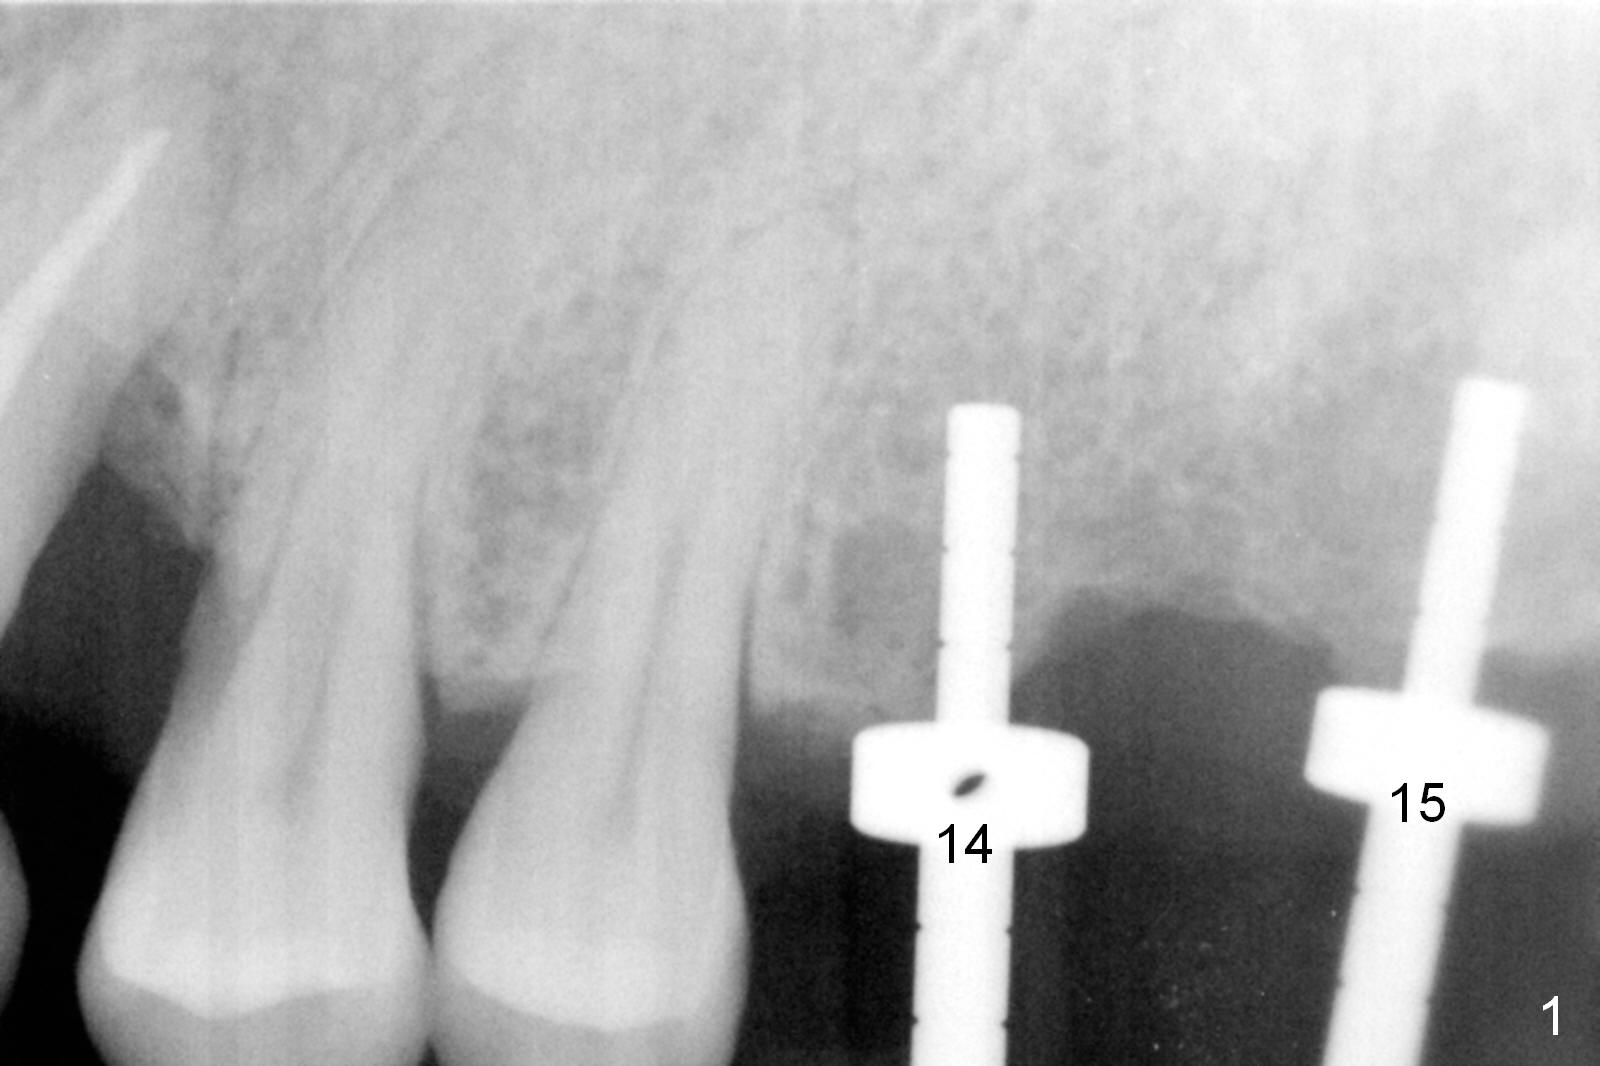

As shown by CT, the ridge at #14 is narrower than that of #15 (confirmed after incision), whereas the density at #14 is higher than that of #15. The osteotomies are established by combination of magic osteotomes and drills after change in trajectory (Fig.1-3). Following placement of 4.5x13 and 5x13 mm IBS implants and 6x4(3) and 6.5x4(3) mm pair abutments at #14 and 15 (Fig.4), flaps are sutured for hemostasis. Since the patient does not tolerate the surgery too well (unstable hypertension and oozing), immediate provisional is delayed. Periodontal dressing is applied instead. While the implants are healing, porcelain chips at the upper anterior bridge. There appears no bone resorption 6 months postop (Fig.5). Impression is taken following changing abutment to 5x4(2) mm at #14 and Diode gingivectomy. A panoramic film is taken 1 year 2 months post cementation. CT taken 2 years post cementation shows relatively good trajectory of these 2 implants (Fig.6,7).